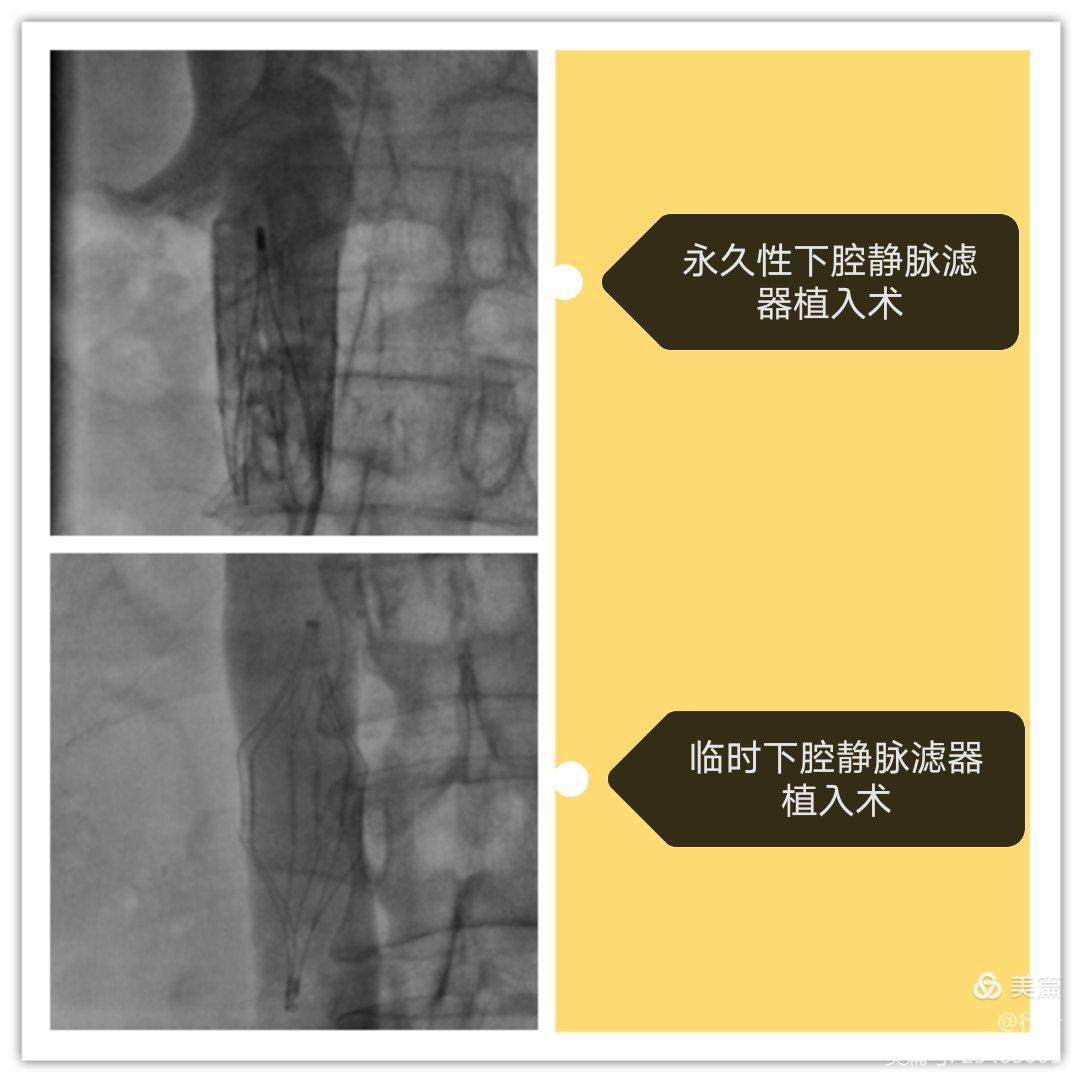

五、下腔靜脈濾器植入術(shù)。